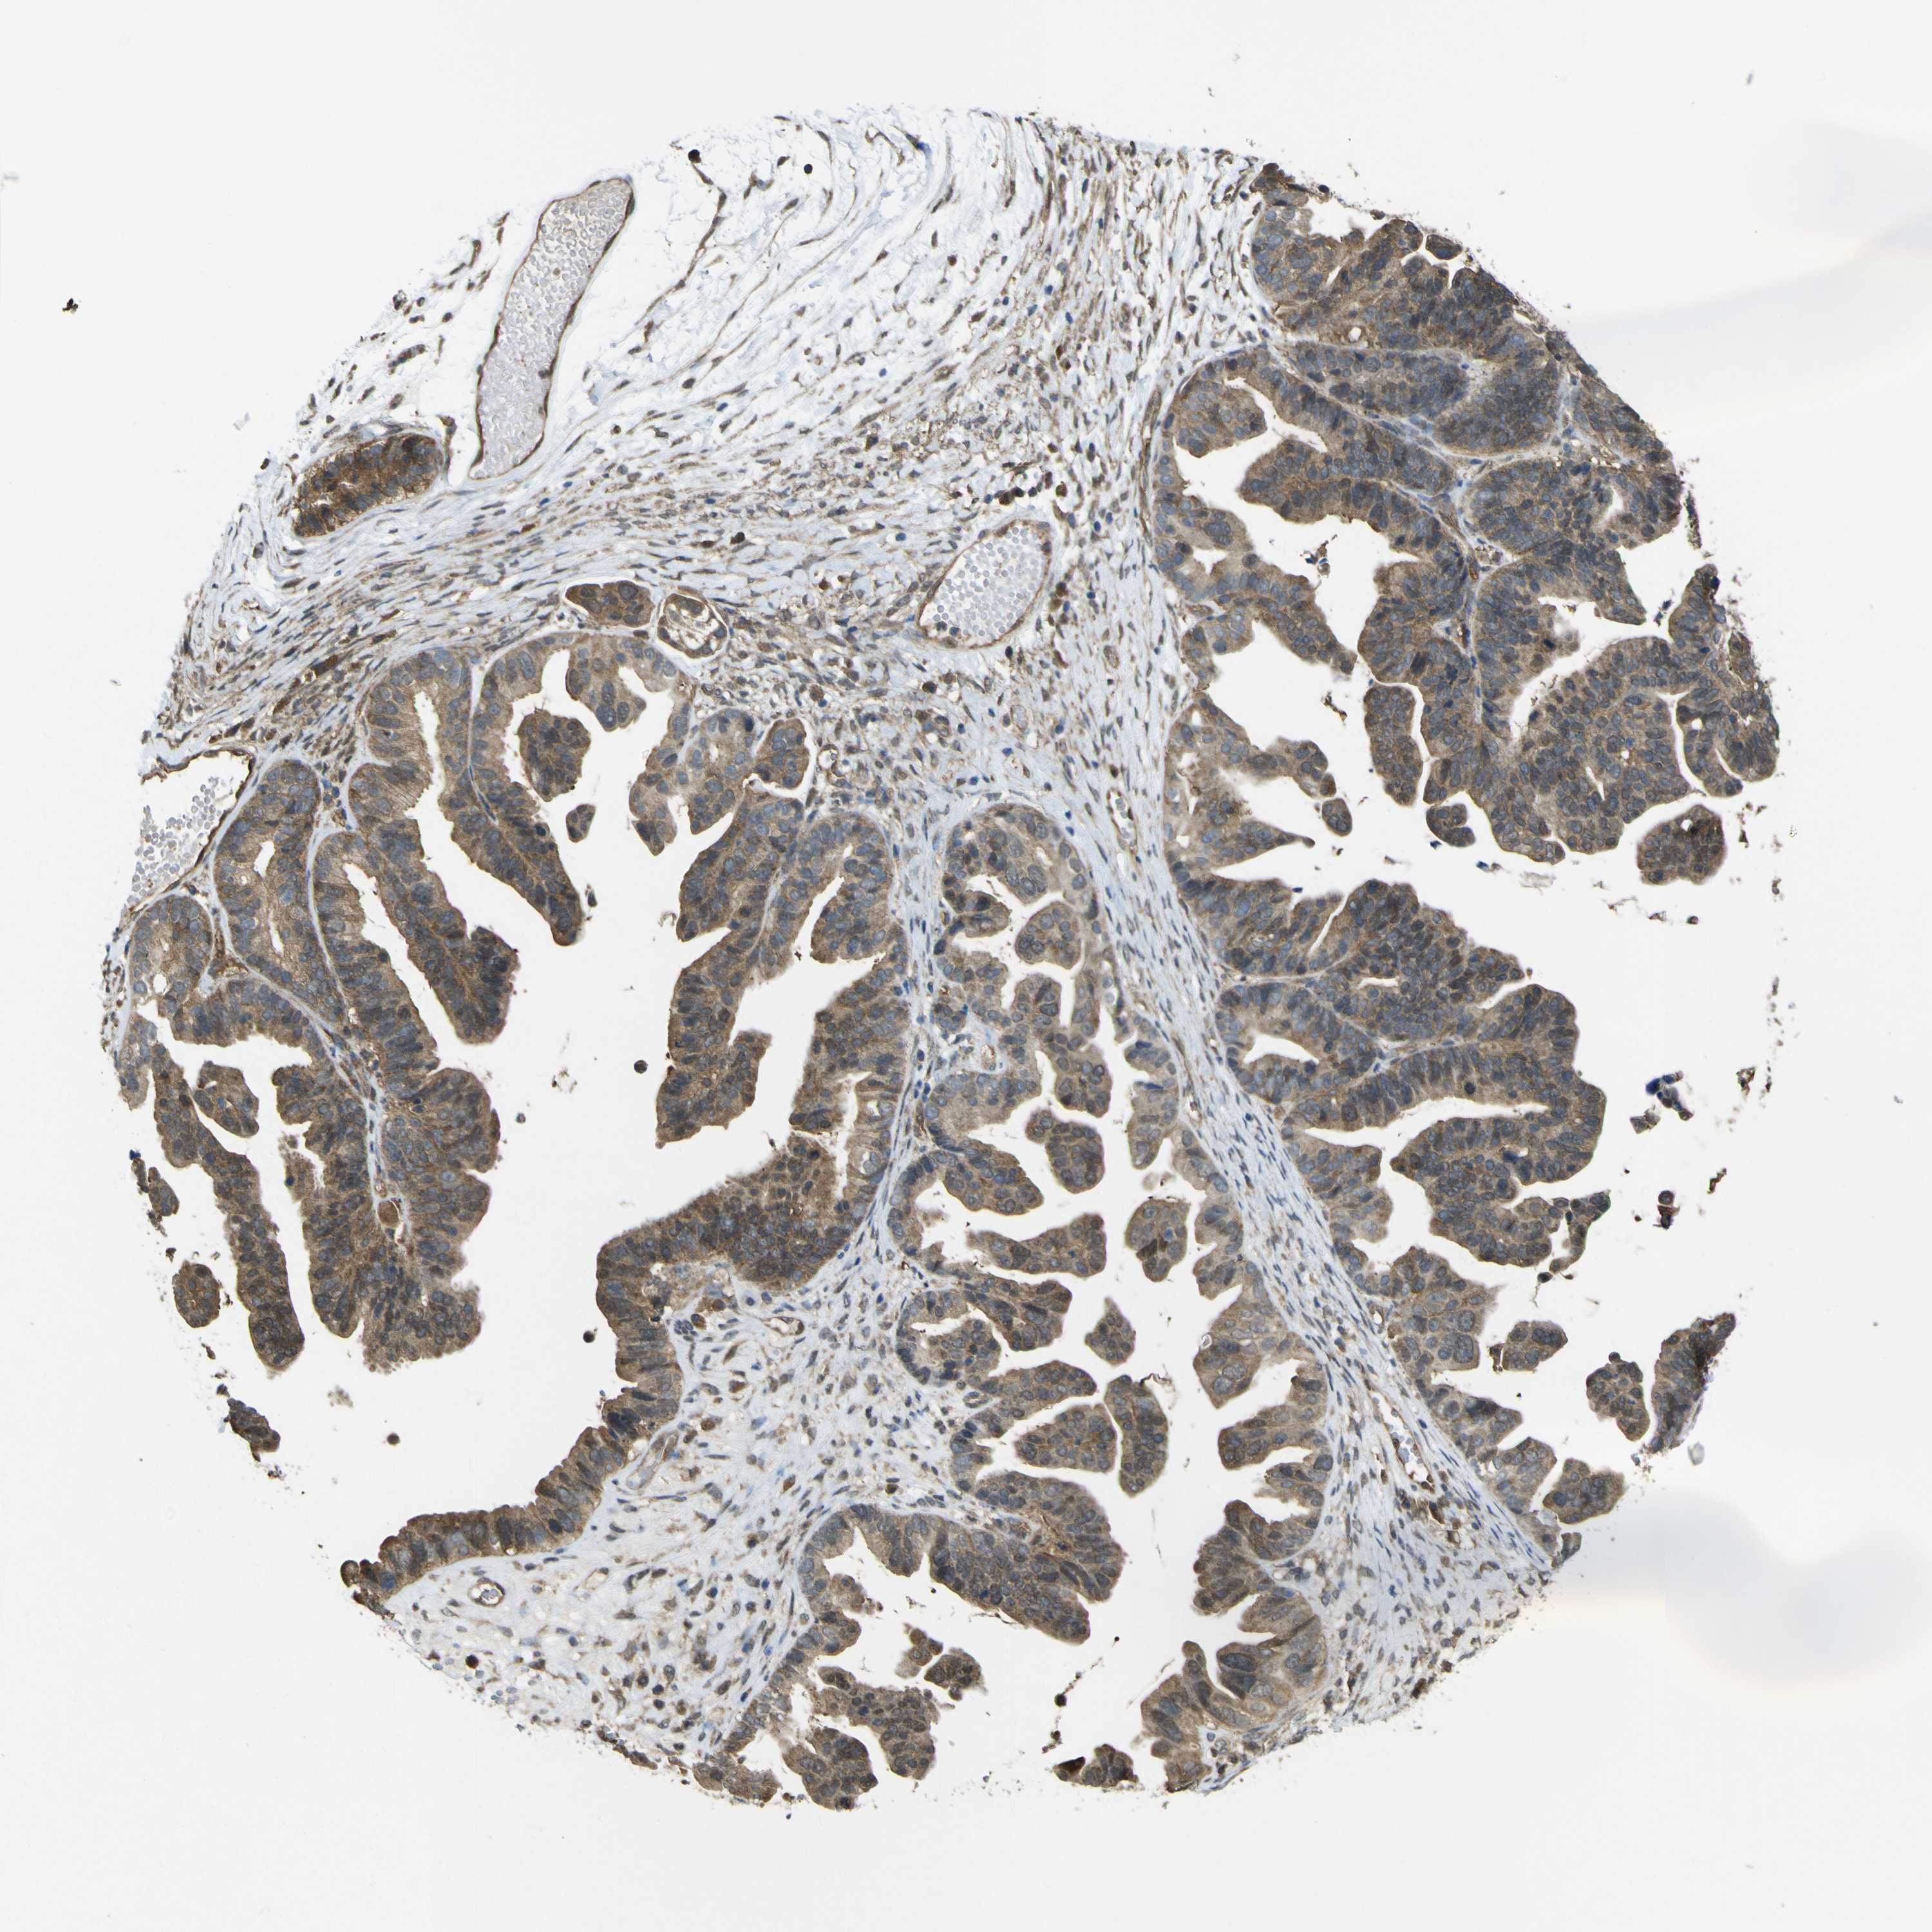

OVARIAN CANCER - Protein expressioni

A mouse-over function shows sample information and annotation data. Click on an image to view it in a full screen mode. Samples can be filtered based on level of antibody staining by selecting one or several of the following categories: high, medium, low and not detected. The assay and annotation is described here.

Note that samples used for immunohistochemistry by the Human Protein Atlas do not correspond to samples in the TCGA dataset.

Antibody stainingi

Antibody staining in the annotated cell types in the current human tissue is reported as not detected, low, medium, or high, based on conventional immunohistochemistry profiling in selected tissues. This score is based on the combination of the staining intensity and fraction of stained cells.

Each image is clickable and will lead to virtual microscopy that enables deeper exploration of all samples and also displays staining intensity scores, fraction scores and subcellular localization as well as patient and tissue information for each sample.

Antibody HPA026918

Antibody CAB013274

Antibody CAB018389

Staining

High

Medium

Low

Not detected

Cystadenocarcinoma, mucinous, NOS